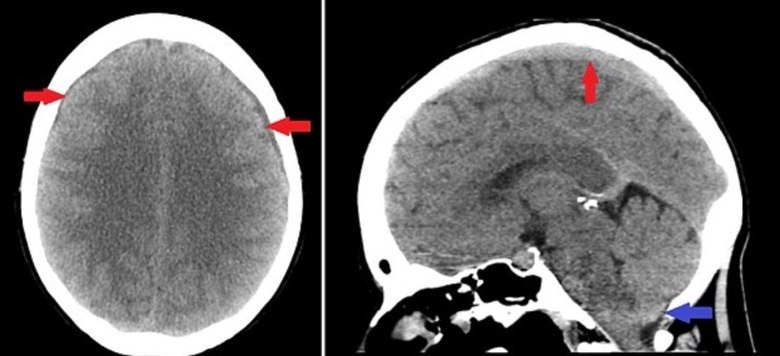

De acordo com o Kings College Hospital, em Londres, exames posteriores mostraram o vazamento de fluído cerebral pela espinha. Isso indicava que ela tinha um rasgo no forro de sua medula espinhal em volta do pescoço

A inglesa de 42 anos sofreu um rasgo no forro da medula espinhal em volta do pescoço